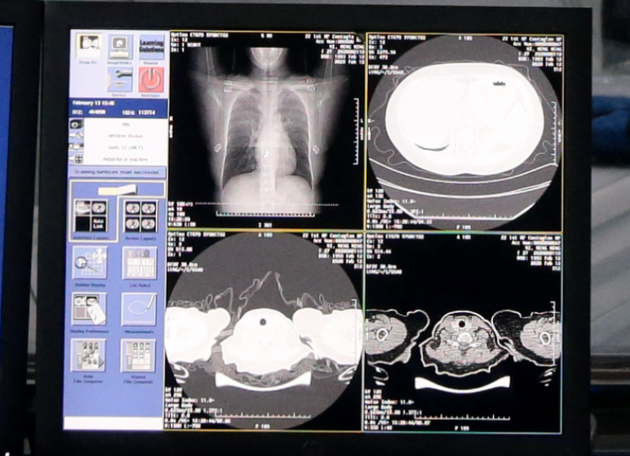

阿里云宣布,疫情期间向全球医院免费开放新冠肺炎AI诊断技术,20秒即可完成一次疑似病例的CT诊断,准确率达96%以上,可帮助海外疫情严重地区大幅节省医疗资源。据了解,这一技术由达摩院研发,已在国内160多家医院上线,累积临床诊断病例超26万例。

这一技术可以辅助医生对CT影像进行分析,20秒内快速鉴别出病灶部分和比例,并量化病例的轻重程度。

对住院病人,还可以用量化分析追踪病灶的变化,帮助医生及时调整治疗方案。